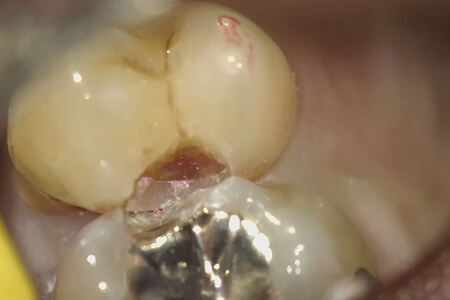

虫歯を取ったあと、虫歯を染めて虫歯が残ってないか確認する。

上の歯に少しピンクに染まる虫歯の部分がマイクロスコープで確認できる。

虫歯を残さず取り除いた状態